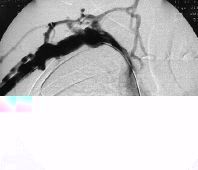

Estenosis venosas en pacientes sometidos a hemodiálisis. Tratamiento mediante prótesis metálicas autoexpansibles

Venous stenoses in patients undergoing hemodialysis. Treatment by means of self-expanding metallic stents